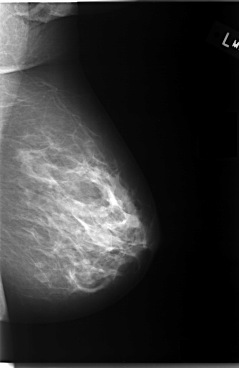

C_0095_1.LEFT_MLO

LEFT_MLO LINES 5880 PIXELS_PER_LINE 3816 BITS_PER_PIXEL 12 RESOLUTION 50 NON_OVERLAY